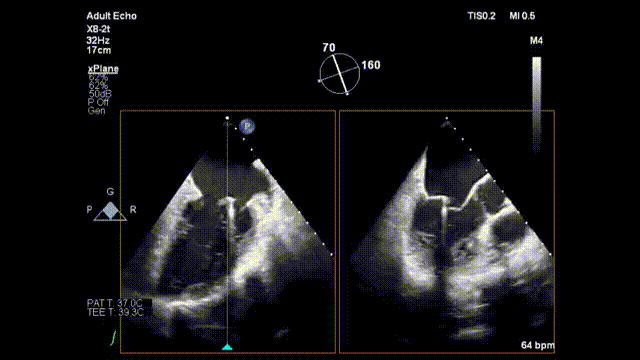

手术正式开始,魏来教授和杨晔医生在心超诊断科董丽莉教授、赵维鹏教授的协助下,仅一个多小时就顺利完成了E-Chord™的穿刺“发射任务”。4根人工腱索被送入朱女士的心脏,准确锚定在二尖瓣脱垂病变区域。然后在超声引导下精确调整人工腱索长度并固定在心尖,从而恢复了朱女士正常的二尖瓣关闭功能。手术完成后朱女士二尖瓣反流立即由重度减少为微量;同时左房平均压明显改善,由术前42mmHg下降到24mmHg。手术全程在超声引导下进行,操作便捷可控,无放射线,心脏不停跳,无需体外循环,创伤小,不出血,恢复快。患者术后2小时即拔除气管插管并返回病房,第二天即可下床活动。

术毕二尖瓣反流减少为微量

至此,E-Chord™已在中山医院圆满完成两例手术。5月27日的首例患者植入3根人工腱索后二尖瓣反流完全消失,3天出院,目前术后15天超声随访结果良好。本次是使用E-Chord™治疗的第二例患者,再次验证了E-Chord™治疗二尖瓣返流的安全性和有效性。